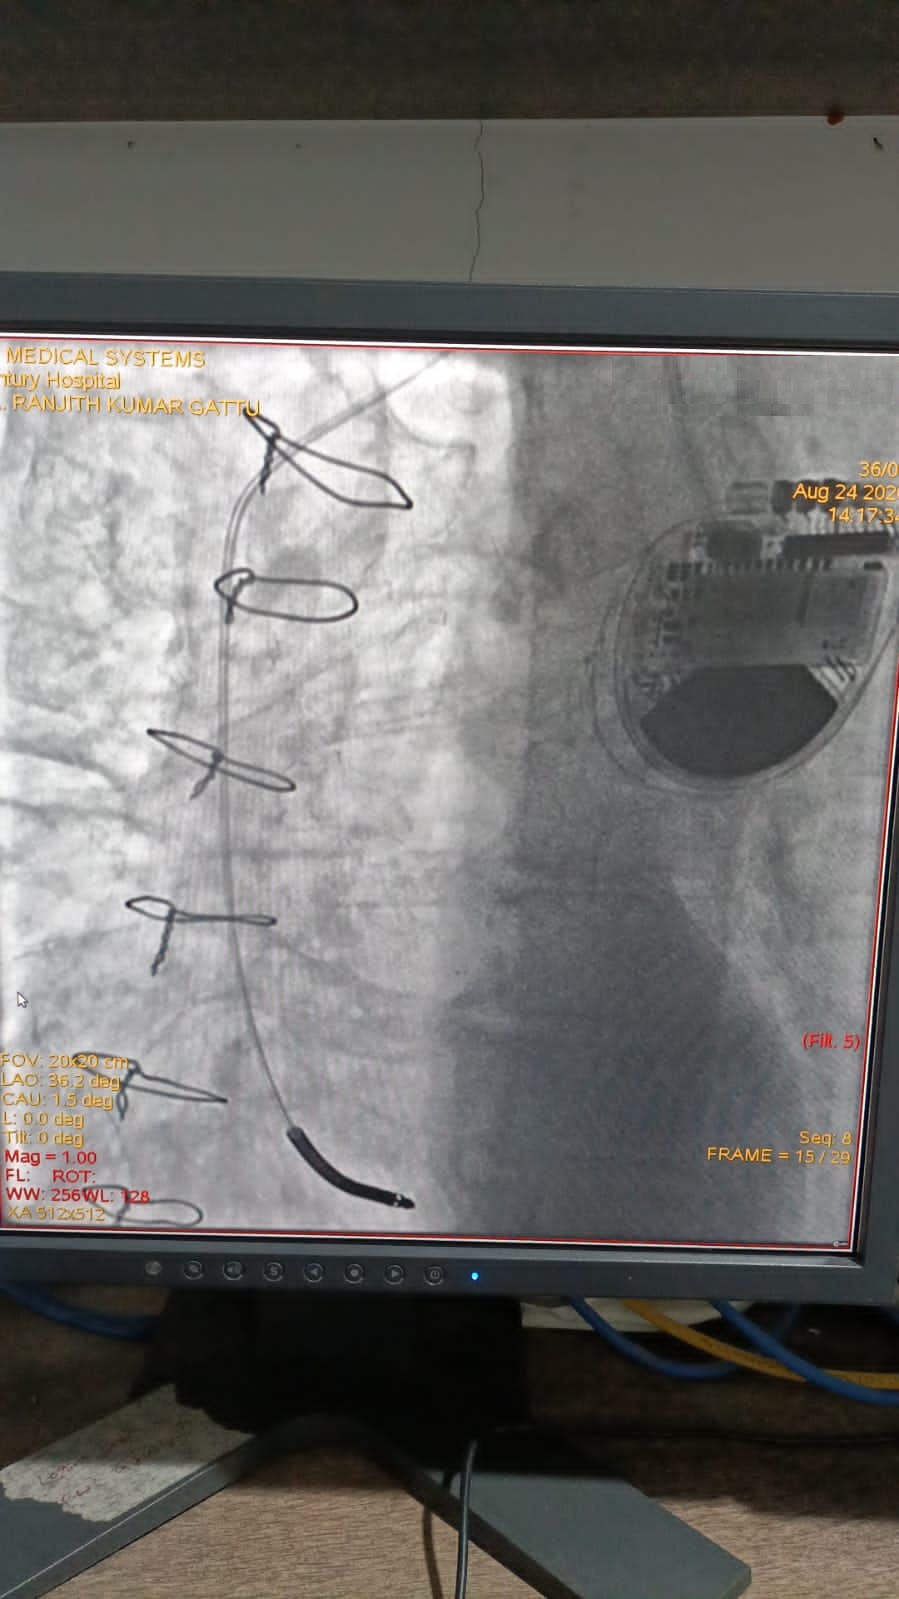

Catheter ablation of arrhythmias

Left Coronary Diseased Artery

Right Coronary Diseased Artery